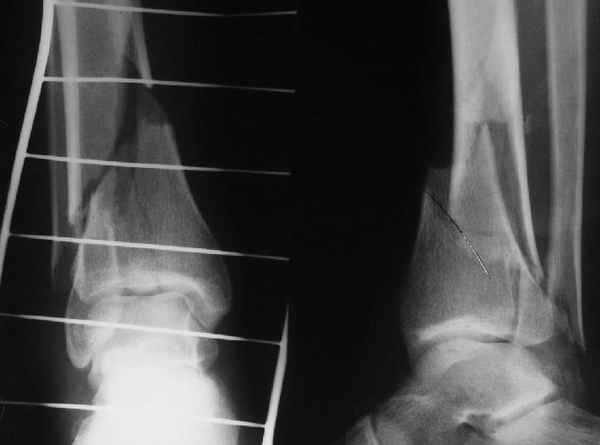

Да и нет! Зависит от перелома и способа остеосинтеза. А результат? (01)

Мы же говорили о проксимальном плече. При переломе tibia, конечно, речи о двух Y-спицах нет. Еще раз о них - пружинящая подвижность без "срезающих" перемещений фрагментов - дополнительный стимул к образованию периостальной мозоли.

А в данном случае - у нас был бы применен locked nail с еще меньшими дырочками на коже и с возможностью полной нагрузки немедленно после операции. Какие тут аргументы в пользу выбора пластины, а не интрамедуллярного гвоздя?